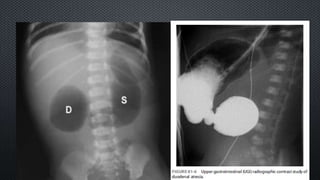

This document discusses intestinal obstruction, its causes, clinical manifestations, diagnosis, and management. Intestinal obstruction is an interruption in the flow of intestinal contents and can be caused by congenital defects, acquired conditions like hernias or tumors, or inflammatory diseases. Patients experience abdominal distension, vomiting, absence of gas or stool, and respiratory distress. Diagnosis involves history, exam, imaging like ultrasound or X-ray, and tests. Treatment consists of IV fluids, gastric decompression, antibiotics, and surgery to remove obstructions or strictures.